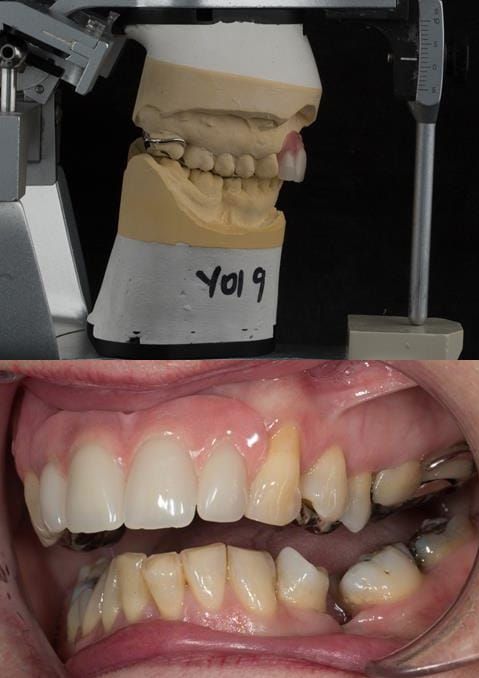

- High smile line showing gum above gingival zeniths of upper front teeth when smiling. Aesthetic failure of the upper four incisors with inflammation of the gingivae and mis-match of the gingival zenith levels.

- Other than the maxillary incisors the remaining dentition was in marginally better condition being moderately to heavily restored. Many will probably require replacement and restoration from time to time mainly from wear and tear owing to occlusal forces.

- Extract the upper 2-2 teeth and replace with an interim acrylic based partial denture. Reline the interim denture over 9 - 12 months, replacing with a definitive cobalt chromium based partial denture. The definitive denture would ideally be designed as an occlusal protective splint to reduce the the potential for mechanical wear and breakages of the moderately/heavily restored maxillary dentition. In addition, should further upper teeth require extraction they could be added on to the denture cobalt chromium framework - therefore a new prosthesis would not be required as future teeth are lost. This option would produce an excellent aesthetic outcome. This is the option the patient chose to have.